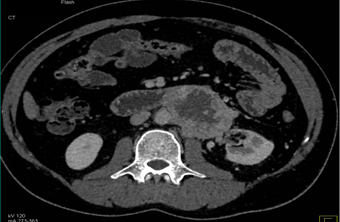

In this mildly hypertensive patient the best diagnosis is?

CTisus Quiz   CTisus Quiz